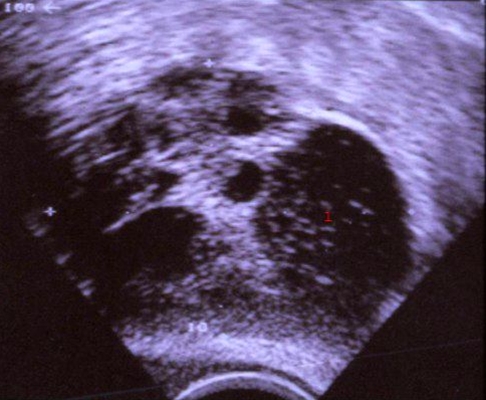

Ultralydskanning af cyste på æggestokken

Æggestok med blandet cystisk-solid proces (dermoid cyste)